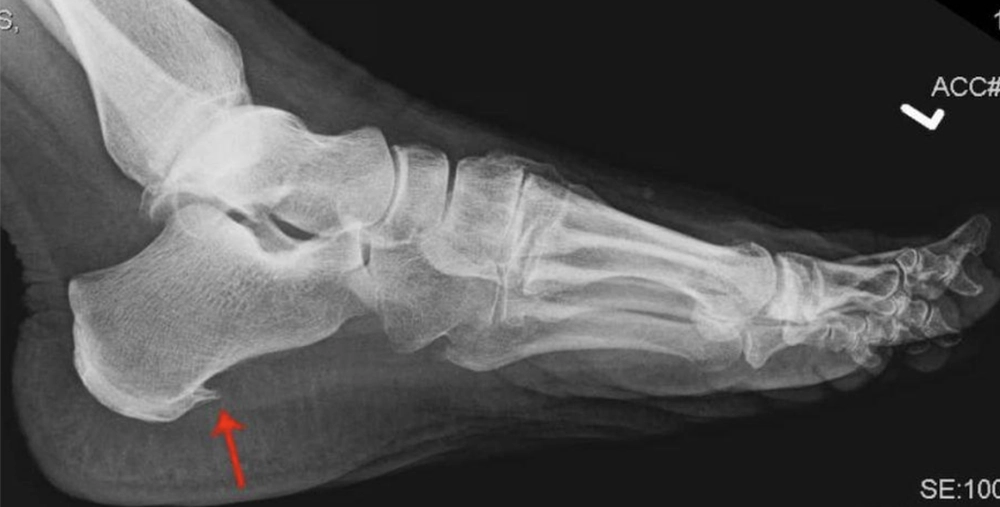

Na grande maioria dos casos o diagnóstico é clínico, porém, em alguns, casos exames de radiografia, ultrassonografia ou até́ a ressonância magnética pode auxiliar o diagnóstico.

O esporão do calcâneo é encontrado em apenas 50% dos casos e não deve ser apontado como causa da dor. Ele é uma calcificação gerada pelo aumento das forças compressivas associadas a tração exercida por alguns elementos plantares (flexor curto dos dedos) no periósteo da tuberosidade plantar.